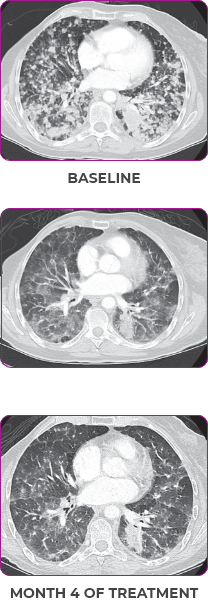

Response in primary and metastatic lesions1

Lung imaging of primary tumors.

SCAN 1: LUNG

SCAN 2: LUNG AND BONE

Images courtesy of Dr Maximilian Hochmair.